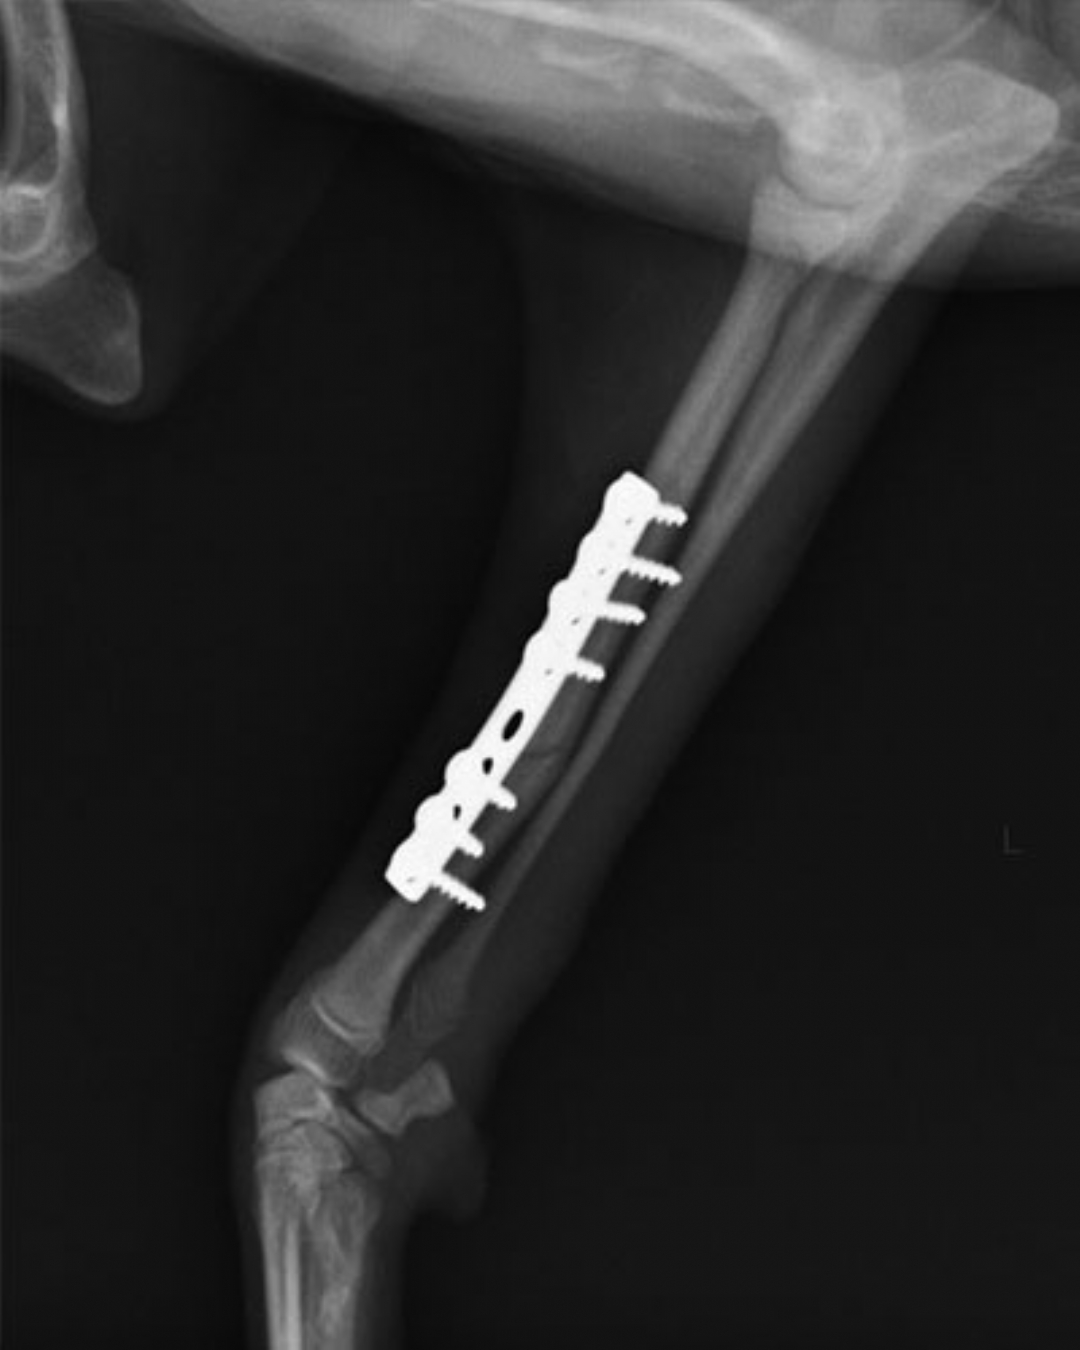

左前肢橈尺骨骨折

一個跳躍後左前肢突然不敢採地的壯壯,經X光確認為左前肢橈尺骨骨折,手術完美復位,目前已可正常行走。

術後